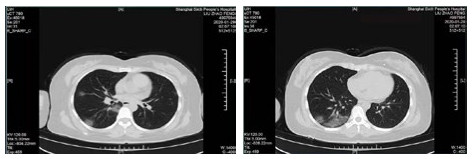

| 图 1 病例1,男性,65岁,沪籍,否认武汉流行病学接触史,发病前2周内每天有大型医院陪护史及疲劳史,既往体健,发热1 d入院,体温38.5℃,无咳嗽症状,无鼻塞,流涕,血白细胞总数及淋巴计数正常,甲乙型流感病毒筛查阴性,新型冠状病毒核酸检测阳性。肺部CT提示双肺多发磨玻璃结节,病灶贴近胸膜,局部小叶间隔增厚,炎症沿支气管血管走向分布,散在小结节影及纤维条索影 Fig 1 Case 1, male, 65 years old, born in Shanghai, denied the history of epidemic exposure of Wuhan. He had a history of accompanying in hospital every day and fatigue in the first two weeks before the onset of the disease. He was hospitalized one day after the onset of fever, with a body temperature of 38.5 ℃, no cough, no nasal obstruction and runny nose, normal WBC and lymph count, negative influenza A and B virus screening, and positive novel coronavirus nucleic acid test. Lung CT showed multiple ground glass nodules in both lungs. The focus was close to pleura, the interlobular septum was thickened, the inflammation distributed along the direction of bronchi and blood vessels, scattered in small nodule shadow and fibrous cord shadow |